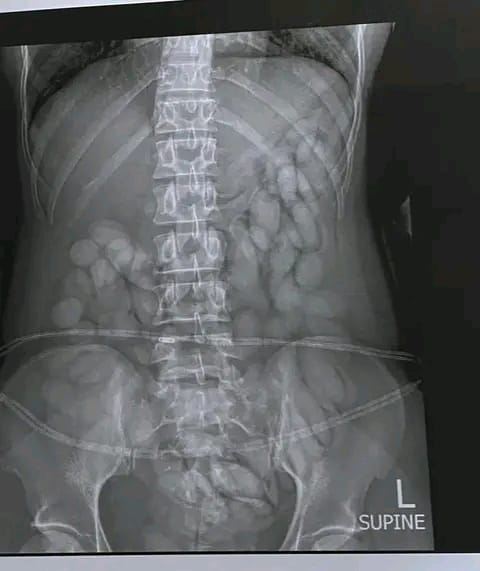

She was at the time found to have swallowed at least 68 bullet looking packets filled with cocaine. A medical examination had confirmed the drugs in her stomach and she was later made to release the drugs.